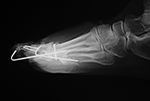

Reconstruction plates have deep notches between

of bending (figure: uniplanar external fixator; figure: fixation plates; figure pelvis reconstruction plates). These plates are often generically referred to as malleable fixation plates. The screw holes are

oval to allow for dynamic compression.

Reconstruction

plates are used mainly for fixation of

pelvic and acetabular fractures. They can also be

used for fixation of distal humeral, clavicular, and finger

fractures (figure: clavicle reconstruction plate; figure: finger reconstruction plate) (Ruedi, 2007; Benjamin, 1994; Wiss, 2013; Berquist, 1995; Freiberg, 2001; Hunter, 2001).